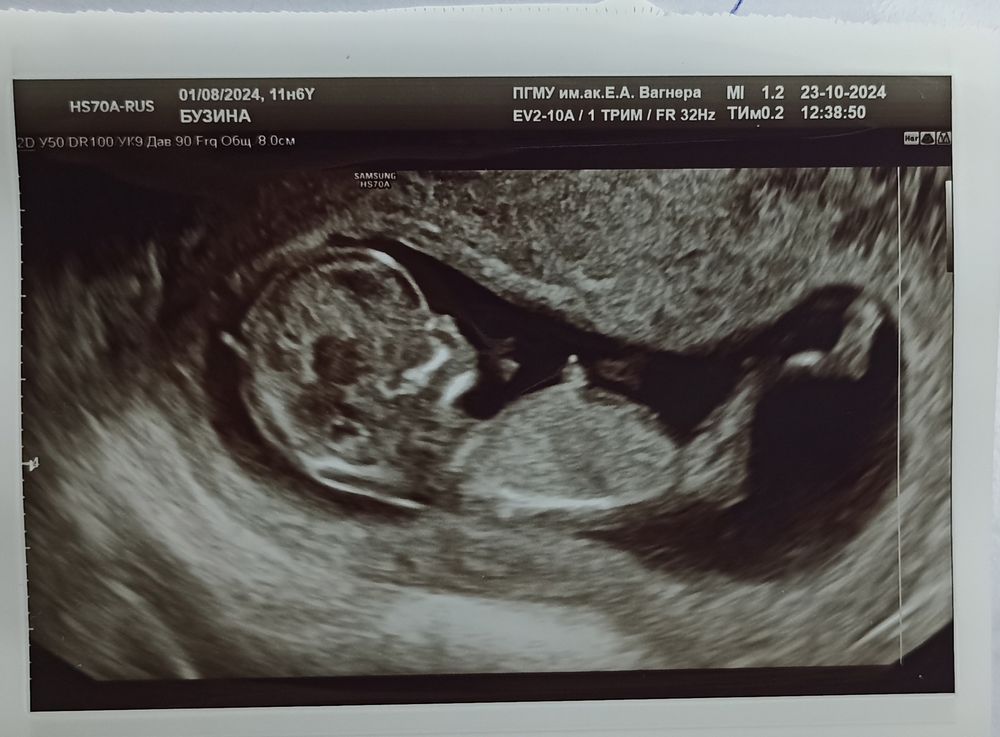

Так же генетики посоветовали переделать Узи платно, но у сертифицированного специалиста и первый названный ими врач, как раз обследовала меня в период планирования беременности. Записалась к ней на повторное узи.

И вот ровно через неделю, успевая в сроки первого скрининга, мы уже вместе с мужем смотрели на нашего малыша и с замиранием сердца и ждали, что скажет врач. Вердикт - кости все на месте, носик просто прелесть, как можно было не увидеть наличие костей в первый скрининг-не понятно.